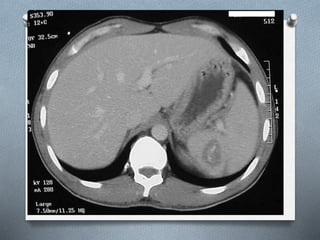

TAC

O Se debe de utilizar solo en el paciente

estable.

O Evalúa el bazo y los órganos vecinos.

O Se utiliza contraste i.v., sin contraste

puede no identificar un sangrado

intraparenquimatoso.

TAC O Se debede utilizar solo en el paciente estable. O Evalúa el bazo y los órganos vecinos. O Se utiliza contraste i.v., sin contraste puede no identificar un sangrado intraparenquimatoso.